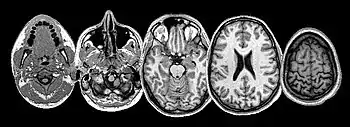

Neuroimaging sheds light on the seat of suffering

Many brain structures and physiological processes are involved in suffering (particularly the anterior insula and cingulate cortex, both implicated in nociceptive and empathic pain).[27] Various hypotheses try to account for the experience of suffering. One of these, the pain overlap theory[28] takes note, thanks to neuroimaging studies, that the cingulate cortex fires up when the brain feels suffering from experimentally induced social distress, as well as physical pain. The theory proposes therefore that physical pain and social pain (i.e. two radically differing kinds of suffering) share a common phenomenological and neurological basis.